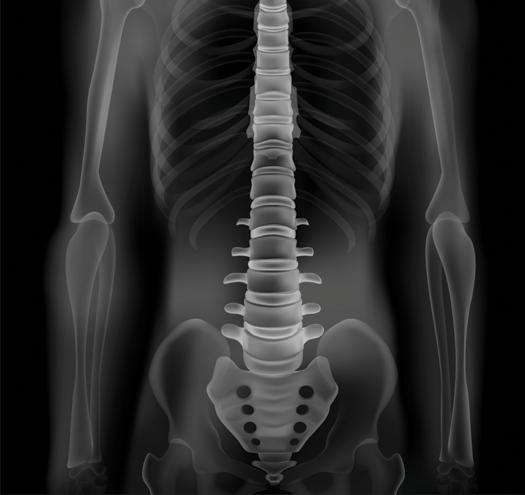

A) Coronal T2 IDEAL, B) axial diffusion tensor imaging (DTI), and C) coronal DTI fiber tracking sequences of the lumbosacral plexus and sciatic nerves demonstrates increased caliber and signal of the right sciatic nerve as it traverses the sciatic notch underneath the piriformis muscle.

D) Prone CT scan of the pelvis at the sciatic notch demonstrates a spinal needle placed at the sciatic nerve with injection of contrast and anesthetic: steroid mixture filling the perineural spaces of the sciatic nerve during a sciatic nerve block.